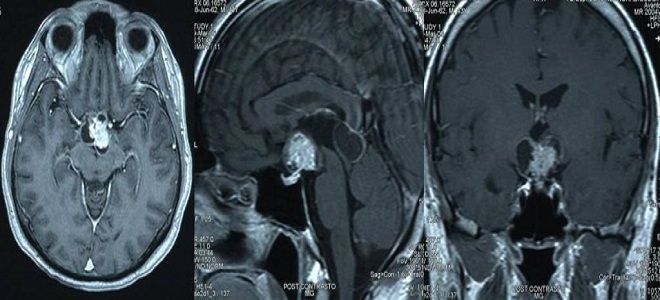

Если нет признаков компрессии спинного мозга, может быть выполнена люмбальная пункция для анализа спинномозговой жидкости. В полученных результатах могут быть обнаружены трепонемы и белковые клетки. Для более точной диагностики нейросифилиса и определения очага инфекции, а также его размеров, часто проводят МРТ. В ходе исследования могут быть выявлены следующие признаки патологии:

- утолщение оболочек мозга;

- гидроцефалия;

- атрофия мозгового вещества;

- наличие гумм.